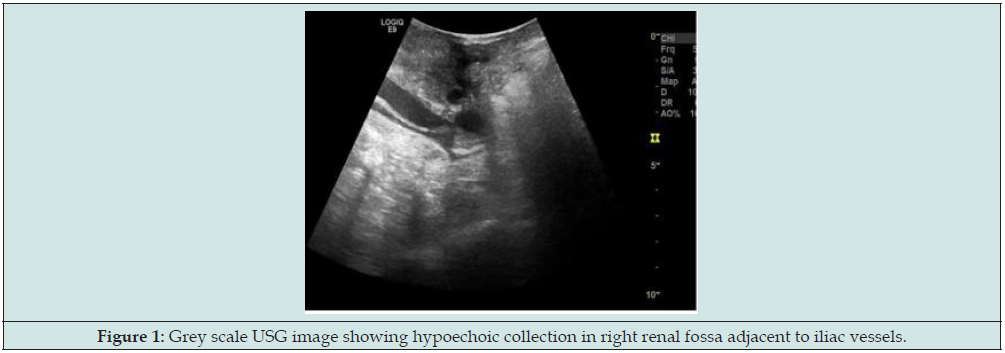

For further evaluation, the patient underwent CT Angiography; finding was necrosis with associated infection/pyonephrosis and non-visualization of transplanted artery and vein. So, the decision to transplant nephrectomy was taken. Transplant nephrectomy was done through retroperitoneal access. Histopathology findings were necrosis of graft with thrombosed vessels and no evidence of fungal infection. The patient presented to transplant surgeon 3 months later with blood discharge from the drain site suture with stable hemodynamics. So, the patient again referred to radiology department for USG evaluation of RIF for possibility of collection. But unfortunately, we found that there was about 5.0x3.4cm size organized hyperechoic collection (Figure 1) and 11x9mm size cystic area within it in basic USG scan. The cystic area shows swirling motion type bidirectional flow continue with right external iliac artery in colour Doppler study (Figure 2). Spectral waveforms demonstrate the classic to and fro flow at neck suggestive of external iliac artery pseudoaneurysm. For further evaluation CT angiography of iliac vessels was prescribed.

Figure 1: Grey scale USG image showing hypoechoic collection in right renal fossa adjacent to iliac vessels.